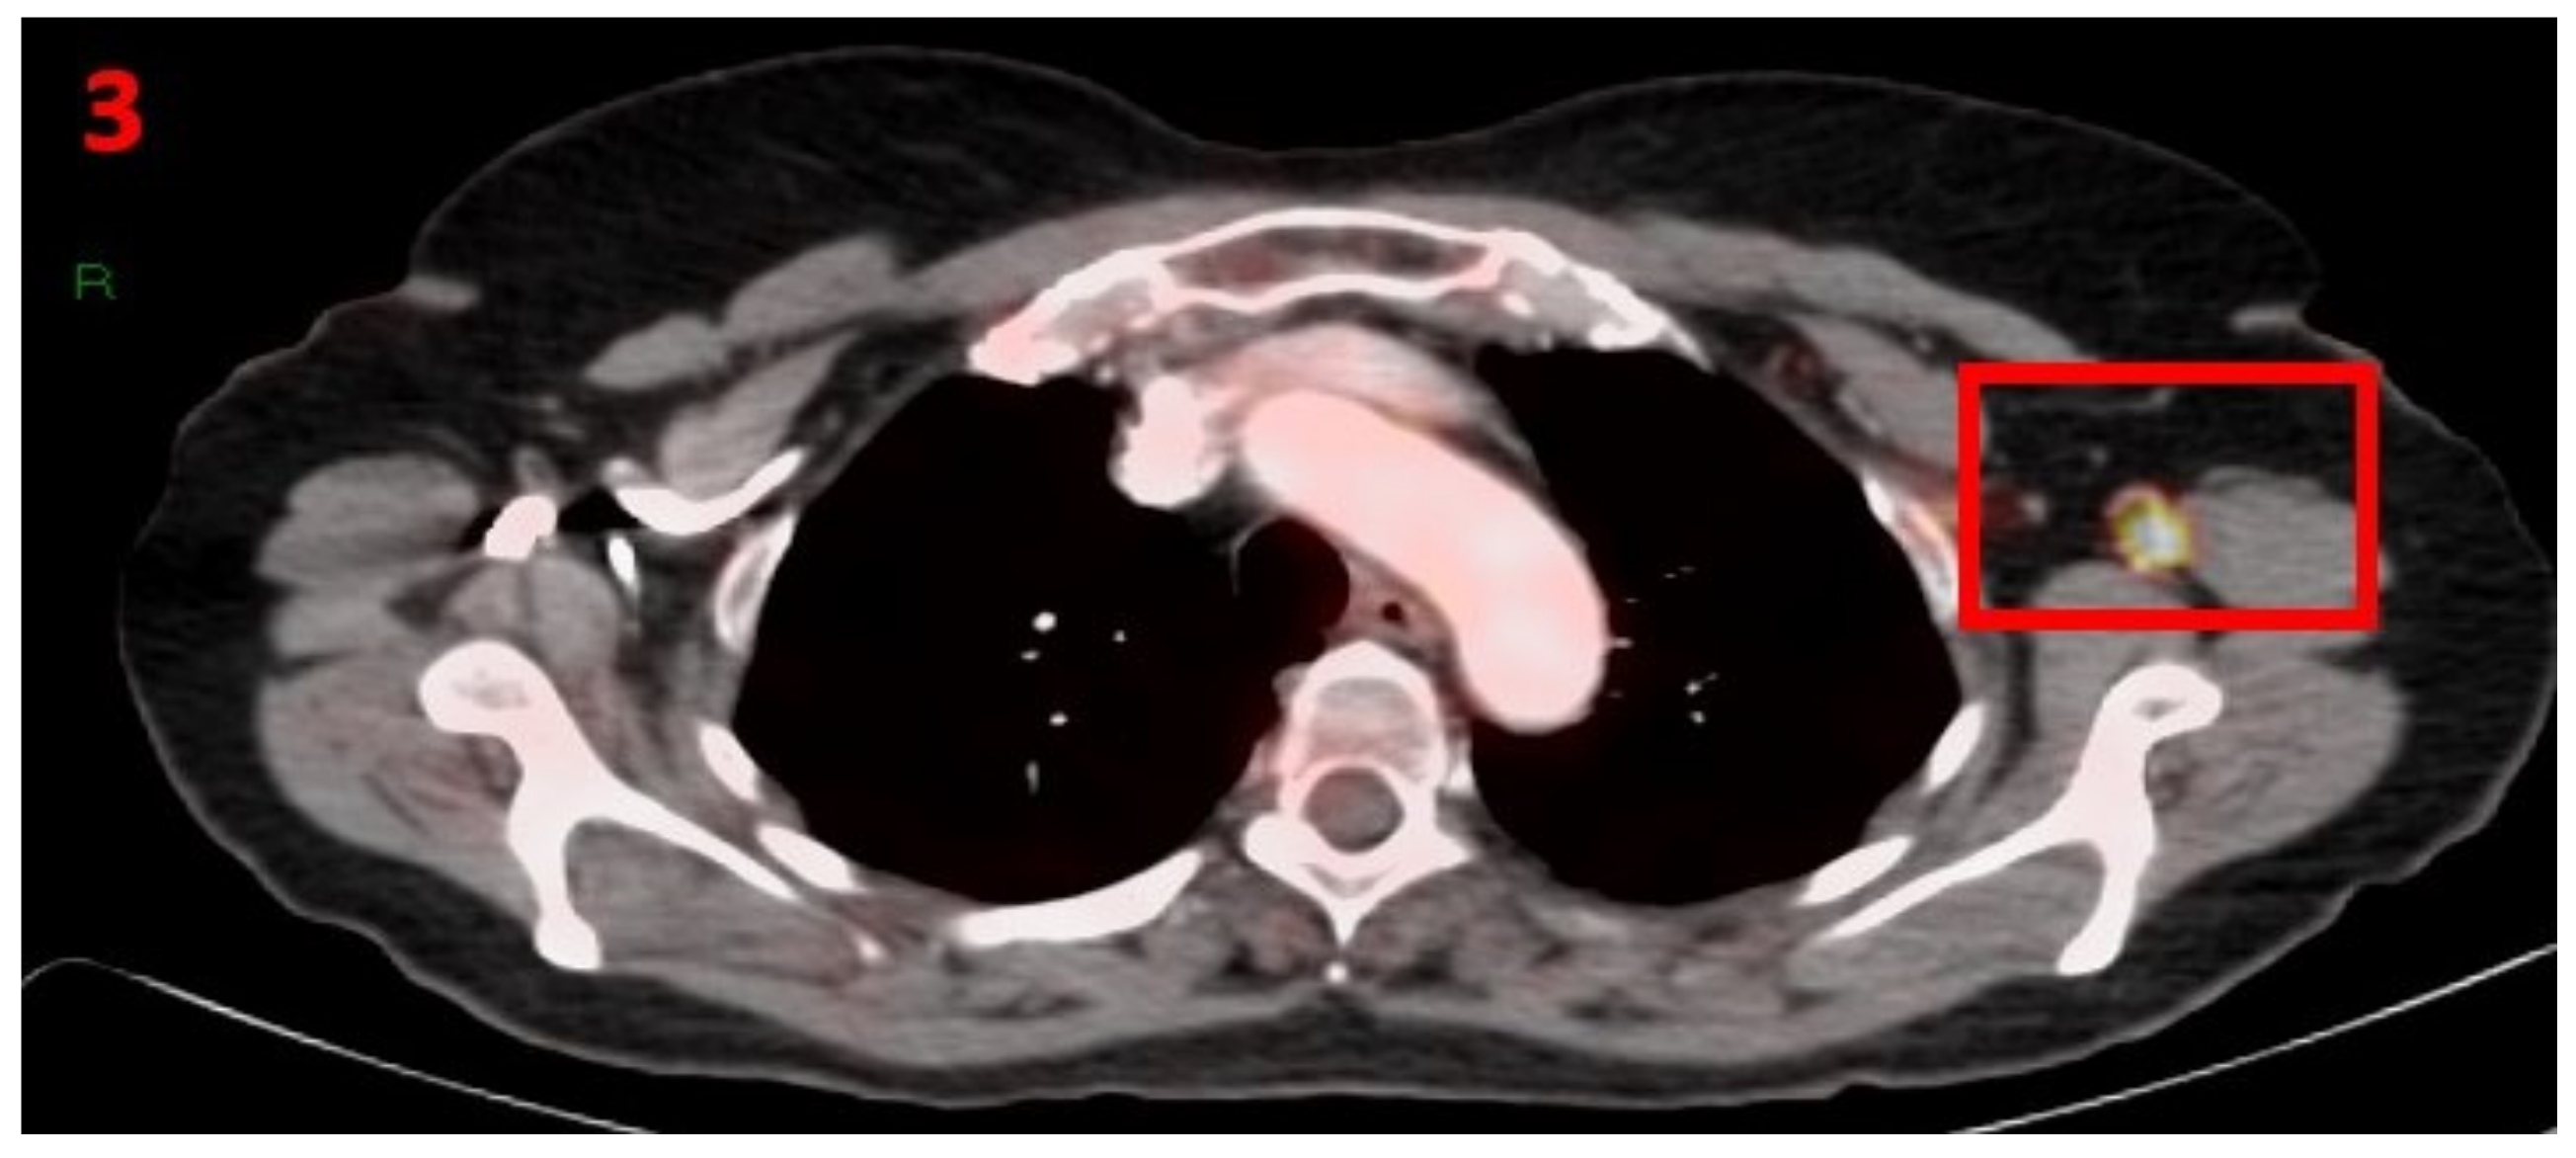

3.3. Case No 3

| Case no.3 | Melanoma | Left arm | 13 days | Hypermetabolic uptake in the left axillary region and lymphadenopathy | Second vaccine | 5 mm | 1 | Pfizer-BioNTech |